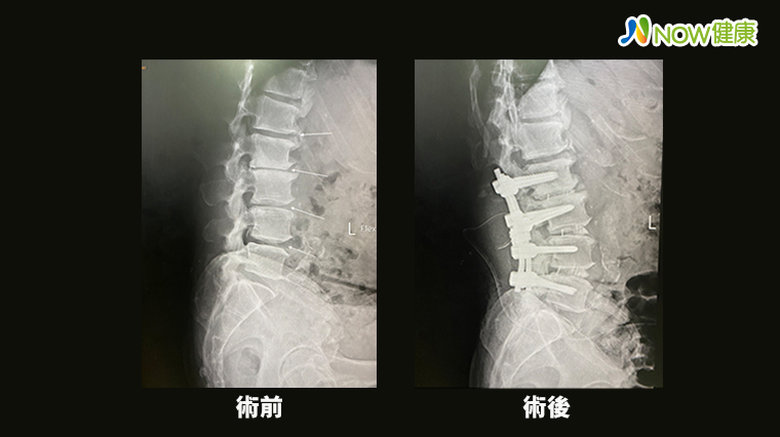

在嘗試保守治療約3年仍未見效果,經朋友介紹至醫院檢查後醫師發現除了骨刺,王先生還有椎間盤突出合併神經壓迫。後來透過微創脊椎減壓及椎體融合手術,症狀改善很多,術後第2天就可下床走路了。

台中長安醫院骨科主任楊志鴻表示,患者的第2至第5節腰椎有很明顯的骨刺及椎間盤突出,也有勞動性側彎問題,這些都會造成神經受到壓迫,因此患者走路會有點一跛一跛的、下肢會痠麻痛。經評估後建議手術治療,術後王先生高興的說 : 「術後痠痛感減輕太多了,也大幅改善生活品質,非常滿意。」

楊志鴻說,傳統的椎體融合手術是靠X光機做判斷,因此神經損傷風險高,此次採用的微創脊椎減壓及椎體融合手術,在電腦斷層3D導航機器幫助下,能精準定位、提升手術的安全性,讓神經損傷機會趨近於零,也縮短癒合時間,因此病患在術後第2天就能下床走路。